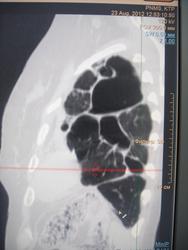

Да, после пульмонэктомии легче живется наверняка, чем с таким пораженным легким. Удалять нельзя в этом случае- недовес, недоедание, ХСН, ДН и куча до сопут заболеваний-  алкоголизм, глухая, как пробка- от препаратов..

Эта форма туберкулеза в классификации поглощается понятием цирротического туберкулеза, который характеризуется разрастанием грубой соединительной ткани в легком и плевре. Понятие цирротического туберкулеза чисто морфологическое, так как в клинике определить наличие именно такого разрастания не представляется возможным. Единственным признаком является постоянное затемнение легочного поля при .многократных рентгенологических исследованиях. В прошлом цирротический туберкулез считали благоприятным исходом заболевания. В настоящее время стали отличать циррозы легких в качестве относительно благоприятных остаточных изменений, в этой рубрике они и числятся в классификации.

Наш опыт пульмонэктомий по поводу цирротического туберкулеза показал, что у всех больных, оперированных с таким диагнозом, имелся активный хронический деструктивный туберкулез, причем каверны располагались действительно среди цирротичеоки измененной легочной ткани (рис. 13). Это позволяет выделить такой вид цирротического туберкулеза, как каварнозно-цирротический или поликавернозно-цирфотический, тотально поражающий легкое, иначе говоря разрушенное легкое.

В клинической классификации рекомендовано относить такие изменения с наличием каверн, с бронхогенными отсевами и бацилловыделением к группе фибвозно-кавернозного туберкулеза. Однако мы считаем, что для такого процесса, при котором тотально поражено целое легкое с полной потерей его нормальной структуры и функции, более подходящим является название разрушенное легкое. Действительно, здесь мы имеем дело уже не с органом, пусть даже патологически измененным, а с его остатками.

Морфологические и мнкробиологические данные показывают, что при разрушенном легком туберкулезной этиологии речь идет об активном торппдно текущем процессе, сопровождающемся вспышками л диссеминацией. В цирротической ткани, окружающей каверны, расположены уязвимые, ломкие, легко подвергающиеся аррозии сосуды, что является основой кровохарканий и профузных кровотечений.

Таким образом, разрушенное легкое диктует необходимость хирургического вмешательства, если нет серьезных противопоказаний.